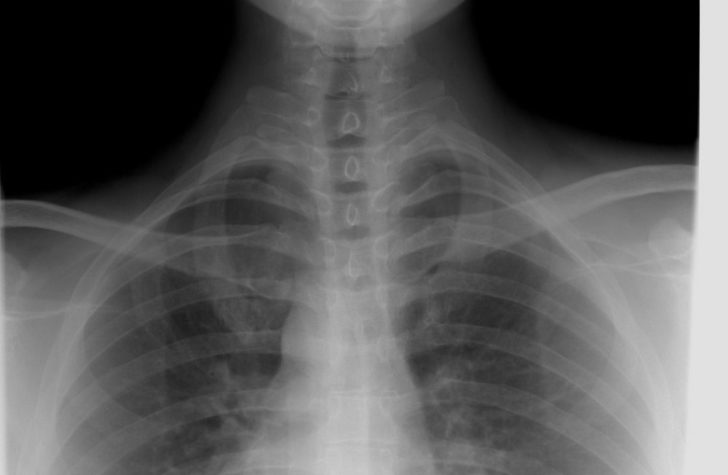

En røntgenundersøgelse er en billeddiagnostisk undersøgelse, hvor man bruger røntgenstråler til at se ind i kroppen. Strålerne passerer gennem vævet, men bliver bremset forskelligt af for eksempel knogler, lunger og bløddele. Et digitalt system opfanger strålerne og omdanner dem til et billede, som lægen kan vurdere.

– at vurdere lunger ved hoste, åndenød, lungebetændelse eller mistanke om anden lungesygdom

Stråledosis ved en almindelig røntgenundersøgelse er lav og svarer ofte til den baggrundsstråling, vi får naturligt fra omgivelserne over dage eller uger. Klinikker, der arbejder efter Sundhedsstyrelsens regler, sørger for, at du kun får den strålemængde, der er nødvendig for at få et godt og brugbart billede.